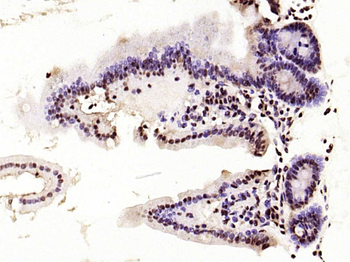

100 μl, 200 μl, 50 μl - RORC Rabbit Polyclonal Antibody [orb6888]Featured